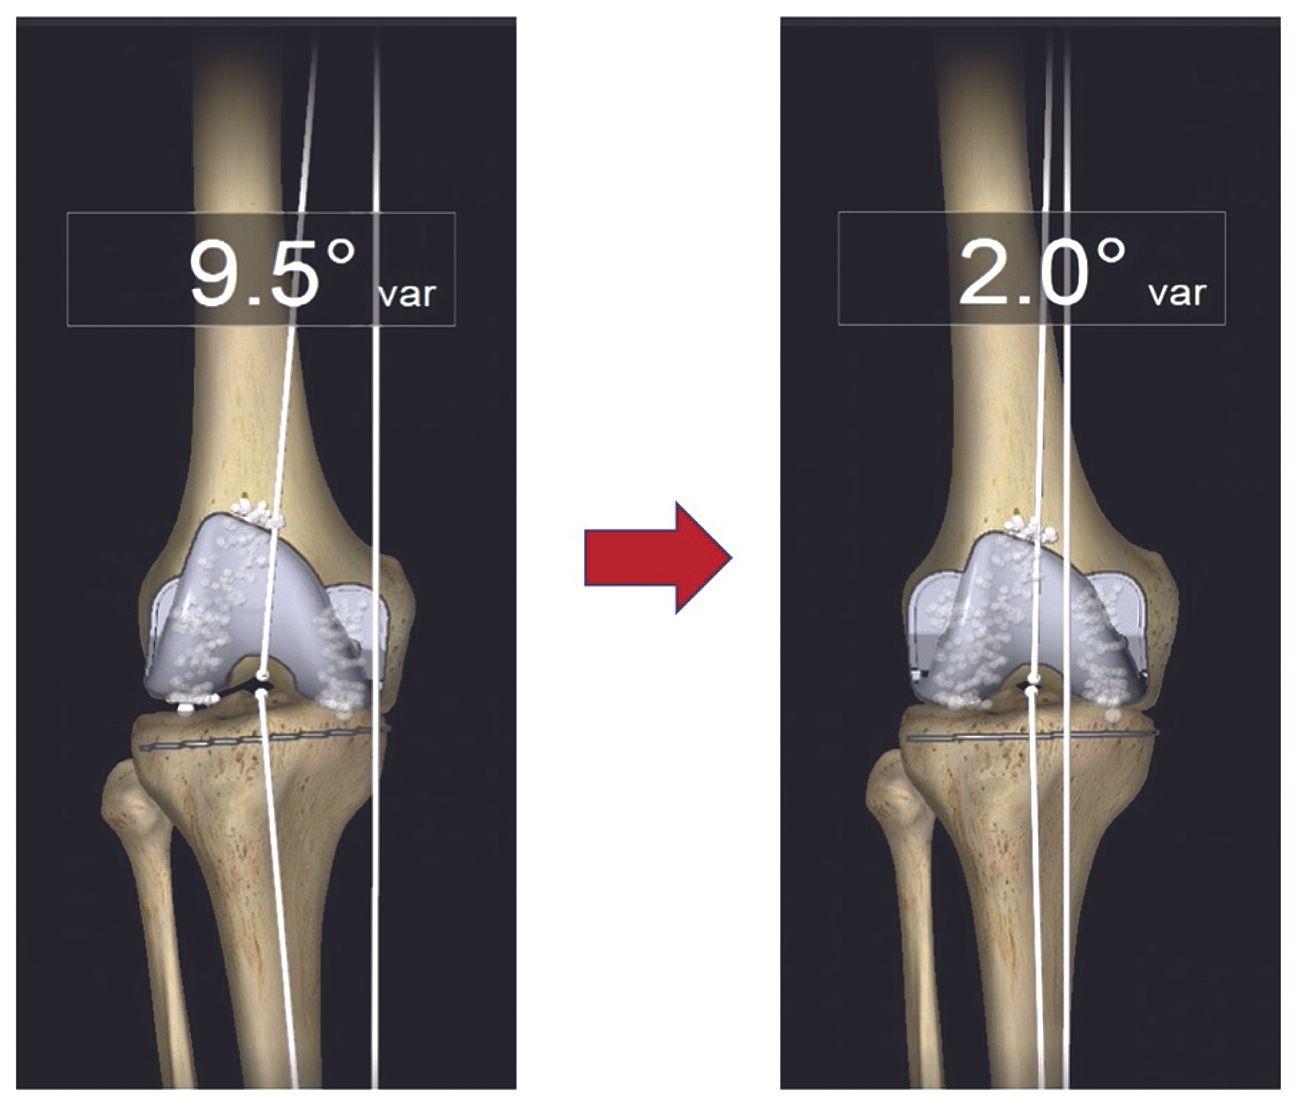

The accompanying articles address advanced reconstruction and emerging technologies across hip and knee surgery. The prosthetic management of coxa vara hips with increased femoral offset and planning and repair of acetabular defects in revision total hip arthroplasty examine solutions to complex anatomical challenges. Attention then shifts to the knee, covering patient-specific alignment and balancing with computer-assisted surgery in total knee arthroplasty and temporary arthrodesis using coupled AO rods. A dedicated contribution further evaluates the clinical integration of mixed reality and artificial intelligence in surgical practice.